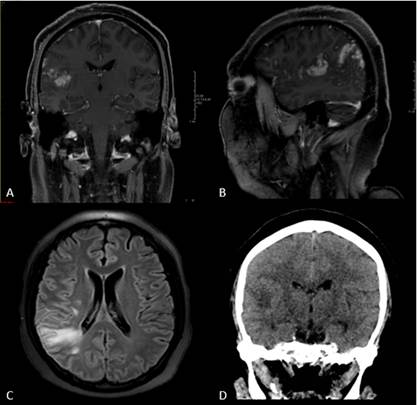

En la Figura 3 A y B se presenta RM encefálica que muestra un tuberculoma, edema en lóbulo parietal derecho y realce meníngeo. En figura 3C RM encefálica en secuencia Flair que muestra alta señal en la sustancia blanca subcortical del lóbulo parietal ascendente y leptomeninge, que refuerzan de forma granular, en anillo. En figura 3D TC cráneo que muestra tuberculoma y edema en base del cráneo, causando disminución del ventrículo derecho por efecto de masa.

Se describen cuatro hallazgos en MTBC: realce meníngeo basal, tuberculomas intracraneales, hidrocefalia e infartos 3, evidenciándose los dos primeros en el paciente.

El realce meníngeo (Figura 3 A y 3B) se explica por el proceso infeccioso a nivel mesencefálico 4, lo que evidenciaría la afectación del descenso de los axones motores, explicando la paresia. El hallazgo de tuberculomas en lóbulo parietal derecho y el edema en base del cráneo (Figura 3) explican la alteración del sensorio y la compresión de la salida de los pares craneales III, IV y VI. Esta última es sugestiva de MTBC debido al compromiso de la base craneal 12.

Los tuberculomas observados en el lóbulo parietal derecho generaron un edema que afectó las áreas de Wernicke y del lenguaje (Figura 3), asimismo, la focalización neurológica es evidencia semiológica de una tumoración cerebral, cuyo diagnóstico etiológico abarca a los tuberculomas. La encefalitis se evidenció clínicamente a partir de la afectación del sensorio, parálisis de pares craneales, vómitos; y la meningitis, por la rigidez de nuca y fotofobia.